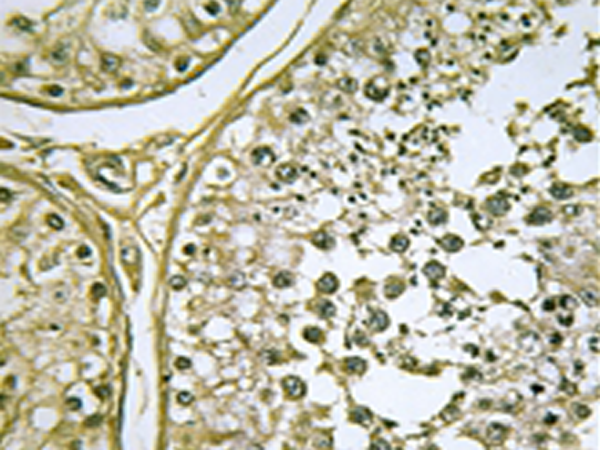

IHC positive control: |

Human testis tissue |

IHC Recommend dilution: |

50-100 |